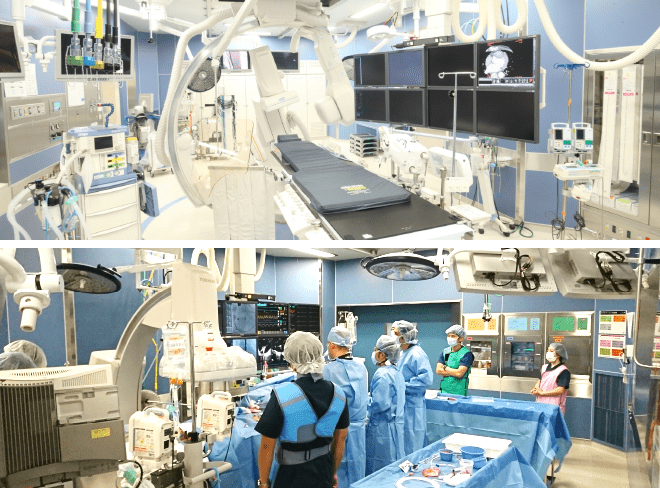

横浜市でも数少ない

ハイブリッドカテーテル室手術室と血管造影装置を統合させたもので、高画質な透視・3D撮影を行うことができる手術室のことをいいます。基本は手術室ですので、感染防止のための配慮、無影灯をはじめとする手術に必要な照明機器も配備しています。これによって、手術のみでは到達困難な部位に対してもカテーテル治療を併用したり、カテーテルのみでは治療できない病変に対しても手術を同時に行うこともできます。また、カテーテル治療中に発生した合併症に対して、外科的手術へ早急に移行できるメリットもあります。当院ではこのハイブリッド手術室を用いたハイブリッド手術を行うことで、患者さんにより低侵襲で効果的かつ安全な治療の提供を目指しております。